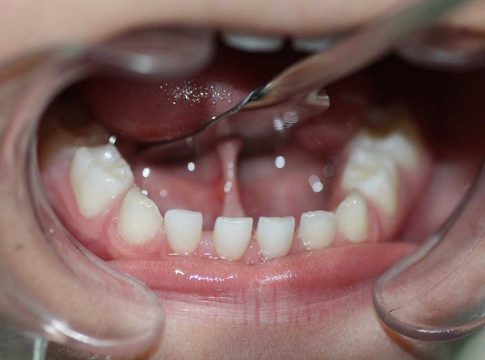

- Paladar muy estrecho, dando lugar a maloclusiones , apiñamiento dental, rotaciones de las piezas dentarias.

- Retrognatia, una mandíbula inferior con una posición atrasada con respecto al maxilar superior.

- Presencia de un diastema en los dos dientes incisivos inferiores.